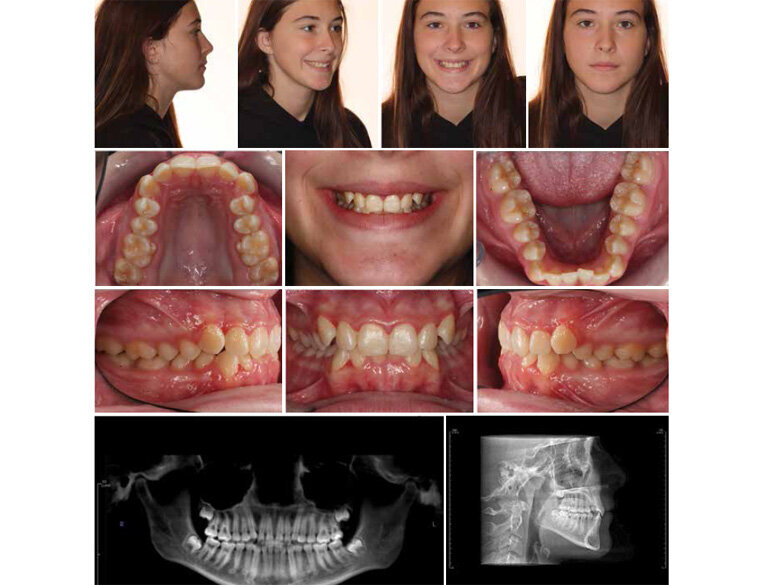

Fig. 4: Initial records. (Photos: Michael J. Mayhew, DDS, MS, MS, & Nicole R. Scheffler, DDS, MS)

The efficiency of Spark Clear Aligners is demonstrated in the following case report. Initial diagnostic records (Fig. 4) were obtained for the patient who offered a chief complaint of “upper front teeth bothering her and getting worse.” Her desire was to have clear aligner treatment and for it to be as fast as possible. The treatment plan included arch width development, uprighting of the teeth and angulation corrections, and ideal alignment with the potential for interproximal reduction. A vibratory intraoral appliance with directions to use 20 minutes per day was utilized with the initial 33 aligners. An additional 16 refinement trays were utilized with treatment completed in eight months (Fig. 5). Appropriate retention appliances were placed with completion of treatment for a very excited and happy patient!